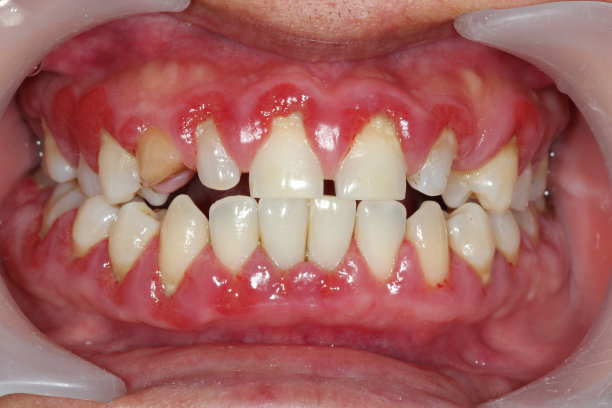

長期服用某種藥物可能引起牙齦增生,臨床表現(xiàn)為牙齦邊緣和牙齦乳頭增生,從_初的小球狀逐漸融合、增大、直到覆蓋部分牙冠。增生部分大多質(zhì)地堅韌,略有彈性,一般不痛、不出血。臨床上鈣離子拮抗劑、抗癲癇藥、免疫抑制劑是引起牙齦增生_常見的藥物。